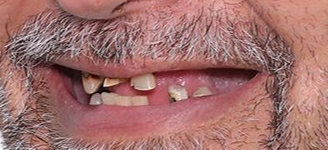

максимально естественный внешний вид

максимально естественный внешний вид